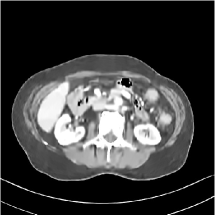

III.C.2. Simulation Framework, Reconstruction Results, and Comparisons

The synthesized low-dose clinical measurements are simulated from regular-dose images at a resolution of mm with a fan-beam CT geometry corresponding to a monoenergetic source at incident photon intensity . The sinograms are of size . The width of each detector column is mm, the source to detector distance is mm, and the source to rotation center distance is mm. We reconstruct images of size with the pixel size being mm mm.

We conducted experiments on one test slice used for parameter tuning (L067-slice 120) and four independent test slices (L109-slice 90, L192-slice90, L333-slice140, L506-slice 100) of the Mayo Clinic data. For PWLS-EP, we ran iterations using relaxed OS-LALM and set regularization parameter . We used the same as the phantom experiments for Algorithm 2. The process of selecting a general set of reconstruction parameters () for the Mayo Clinic test slices is identical to that for the XCAT phantom in Section III.B.2. The selected regularization parameter and the parameters that control the sparsity of the coefficient maps are for ST, , , , , for MARS2, , , , , , , for MARS3, , , , , , , , , , , for MARS5, and , , , , , , , , , , , , , , for MARS7, respectively.

Figs. 8, 9, 10, and 11 show the reconstructions of the four independent slices using the FBP, PWLS-EP, PWLS-ST, PWLS-MARS2, PWLS-MARS3, PWLS-MARS5, and PWLS-MARS7 schemes, respectively. Additional Mayo Clinic experimental results of the parameter tuning case (Fig. 15) are shown in the supplementary document. Table 1 lists the RMSE and SSIM values of reconstructions of the four independent test slices, with the best values bolded. Generally, the five and seven layer models provided the best RMSE and SSIM values. They outperform the single-layer model by HU in RMSE on average. However, the MARS5 and MARS7 models perform similarly. In order to strengthen the benefits of the multi-layer model, Table 2 lists the RMSE of the reconstructions in four different ROIs (shown in the reference of Fig. 11) with seven methods for slice 100 of patient L506. By observing the reconstructed images, we see that although the ST model achieves a cleaner reconstruction result than FBP and PWLS-EP, it still sacrifices some sharpness of the central region and suffers from loss of details. The deeper models have a somewhat more positive effect in terms of maintaining subtle features, which is clearly more essential to clinical diagnosis. Furthermore, as we will discuss later, after considerable parameter tuning, we found that the information contained in residual maps is gradually decreased with the number of layers, eventually vanishing at some layer, which suggests that very deep unsupervised models might not offer significantly better image quality.